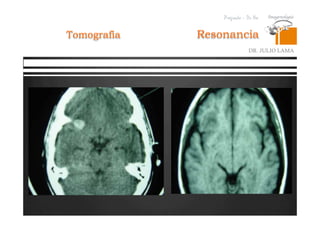

Resonancia

DR. JULIO LAMA

Tomografia